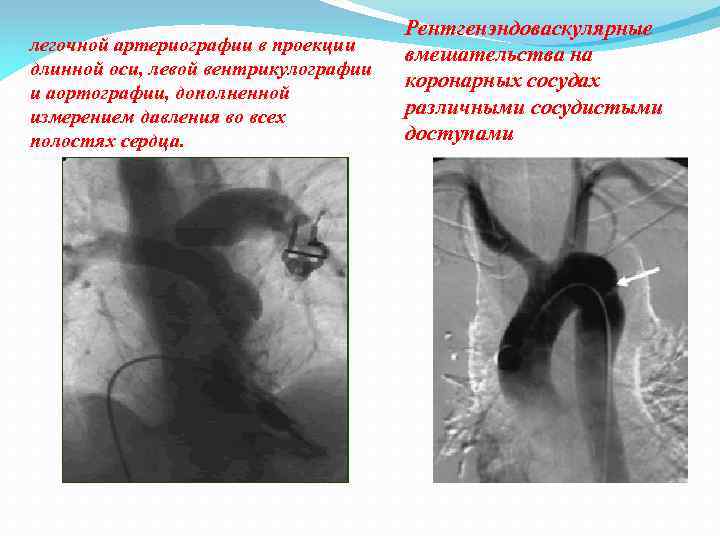

легочной артериографии в проекции длинной оси, левой вентрикулографии и аортографии, дополненной измерением давления во всех полостях сердца. Рентгенэндоваскулярные вмешательства на коронарных сосудах различными сосудистыми доступами